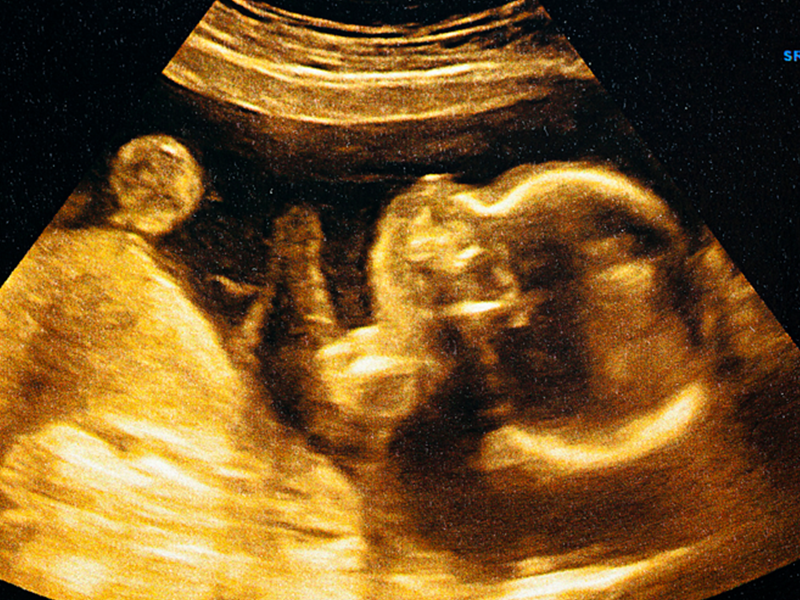

B超检查医生说胎儿头偏大,暗示可能存在胎儿生长过度、胎儿畸形等情况,也不排除与遗传因素、胎儿脑积水、脑肿瘤有关,可能会对宝宝的发育造成影响,可咨询医生进行相应的处理,必要时应终止妊娠。

网传做B超检查时医生说胎儿头大是在暗示生男孩,但其实并不是这样的,胎儿头大和生男生女没有任何的关系,一般胎儿头部的大小是通过双顶径的检查得知,这项检查主要是为了知晓胎儿的发育情况是否正常,并不能判断胎儿的性别,而且胎儿的性别是在受精的那一刻起就已经决定好了的,这和胎儿的头大小是没有关系的。

由于孕期各阶段胎儿的发育不同,每个孕妇的体质也不同,因此胎儿的发育不可避免地会有所不同,可能会导致头大的现象,而有些孕妇认为胎儿头大就是在暗示生男孩,那么这到底是真是假呢,具体可看以下分析:

其实孕期检查出胎儿头大与胎儿的性别是没有任何关系的,看不出生男孩还是生女孩,通常造成胎儿头大的原因有以下几点,孕妇可以先去医院做检查,找出原因后再针对性进行调理: